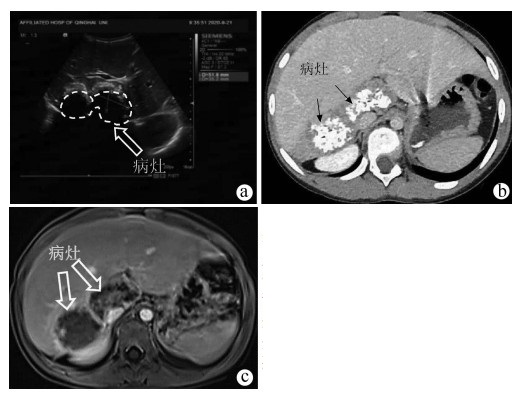

胰腺内副脾误诊为胰腺神经内分泌肿瘤1例报告

夏旭翔, 吕国悦, 仇晓桐, 邱伟

2022, 38(2): 436-438. DOI: 10.3969/j.issn.1001-5256.2022.02.036

摘要(1199) HTML (864) PDF (2885KB)(61)

摘要: